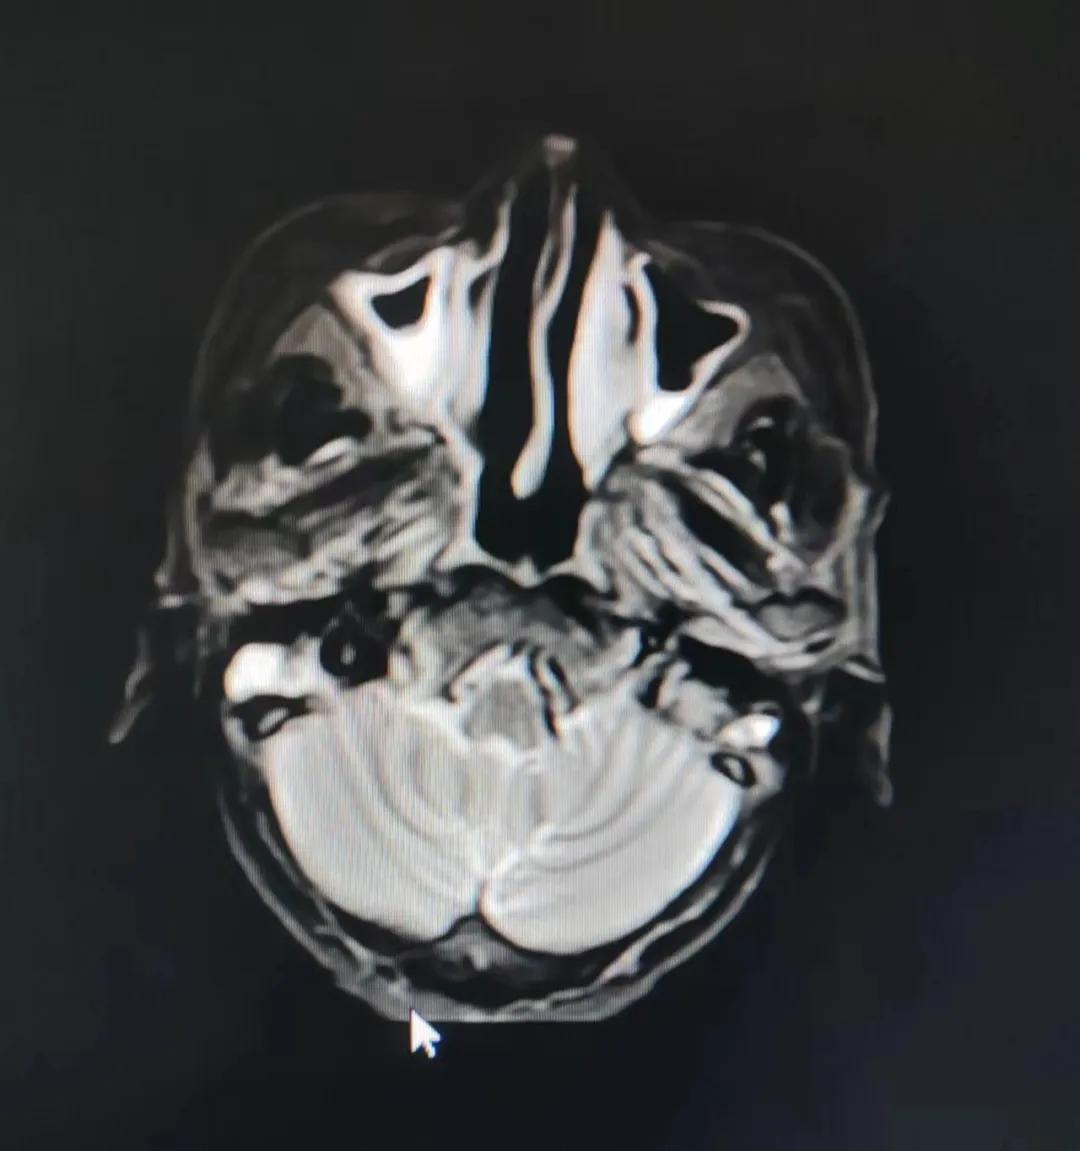

治療后

放療結(jié)束,除了放療處的皮膚輕微放射性皮炎外,基本沒有什么不良反應(yīng)。復(fù)查發(fā)現(xiàn),鼻腔淋巴瘤已不可見,目前患者已康復(fù)出院。